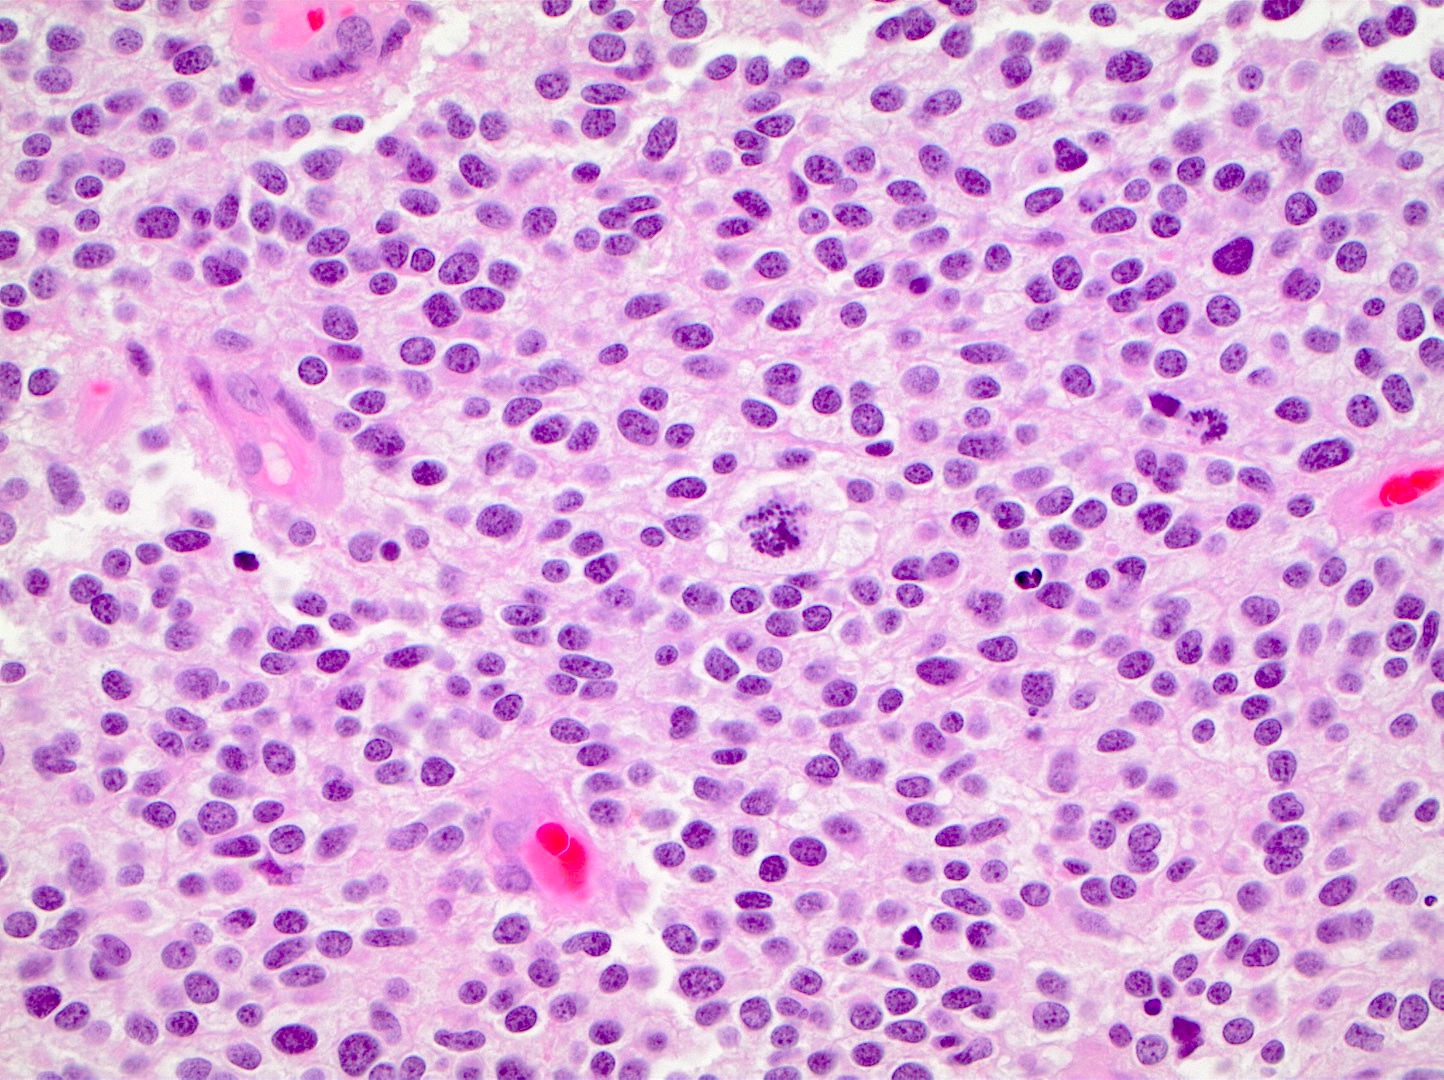

Microscopic (histologic) description

- Closely packed cells with small, round, monotonous nuclei (slightly larger than a normal oligodendrocyte)

- Perinuclear clearing (fried egg appearance)

- Formalin fixation artifact

- Will not be seen on frozen sections or smear preparations

- Network of thin walled, branching blood vessels (chicken wire vasculature)

- Microcalcifications (calcospherites) are characteristic

- Presence of perineural, perivascular or subpial aggregates of tumor cells (secondary structures of Scherer)

- Occasional mitoses and moderate nuclear atypia are still consistent with grade 2 designation (J Neuropathol Exp Neurol 2001;60:248)

- Not uncommon to find well differentiated / fibrillary astrocytic morphology (Acta Neuropathol 1984;64:265)

Microscopic (histologic) images

Contributed by Jared T. Ahrendsen, M.D., Ph.D. and John DeWitt, M.D., Ph.D.